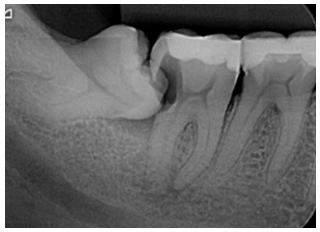

Analise a imagem a seguir.

O nome e a principal indicação desse exame radiográfico são, respectivamente: